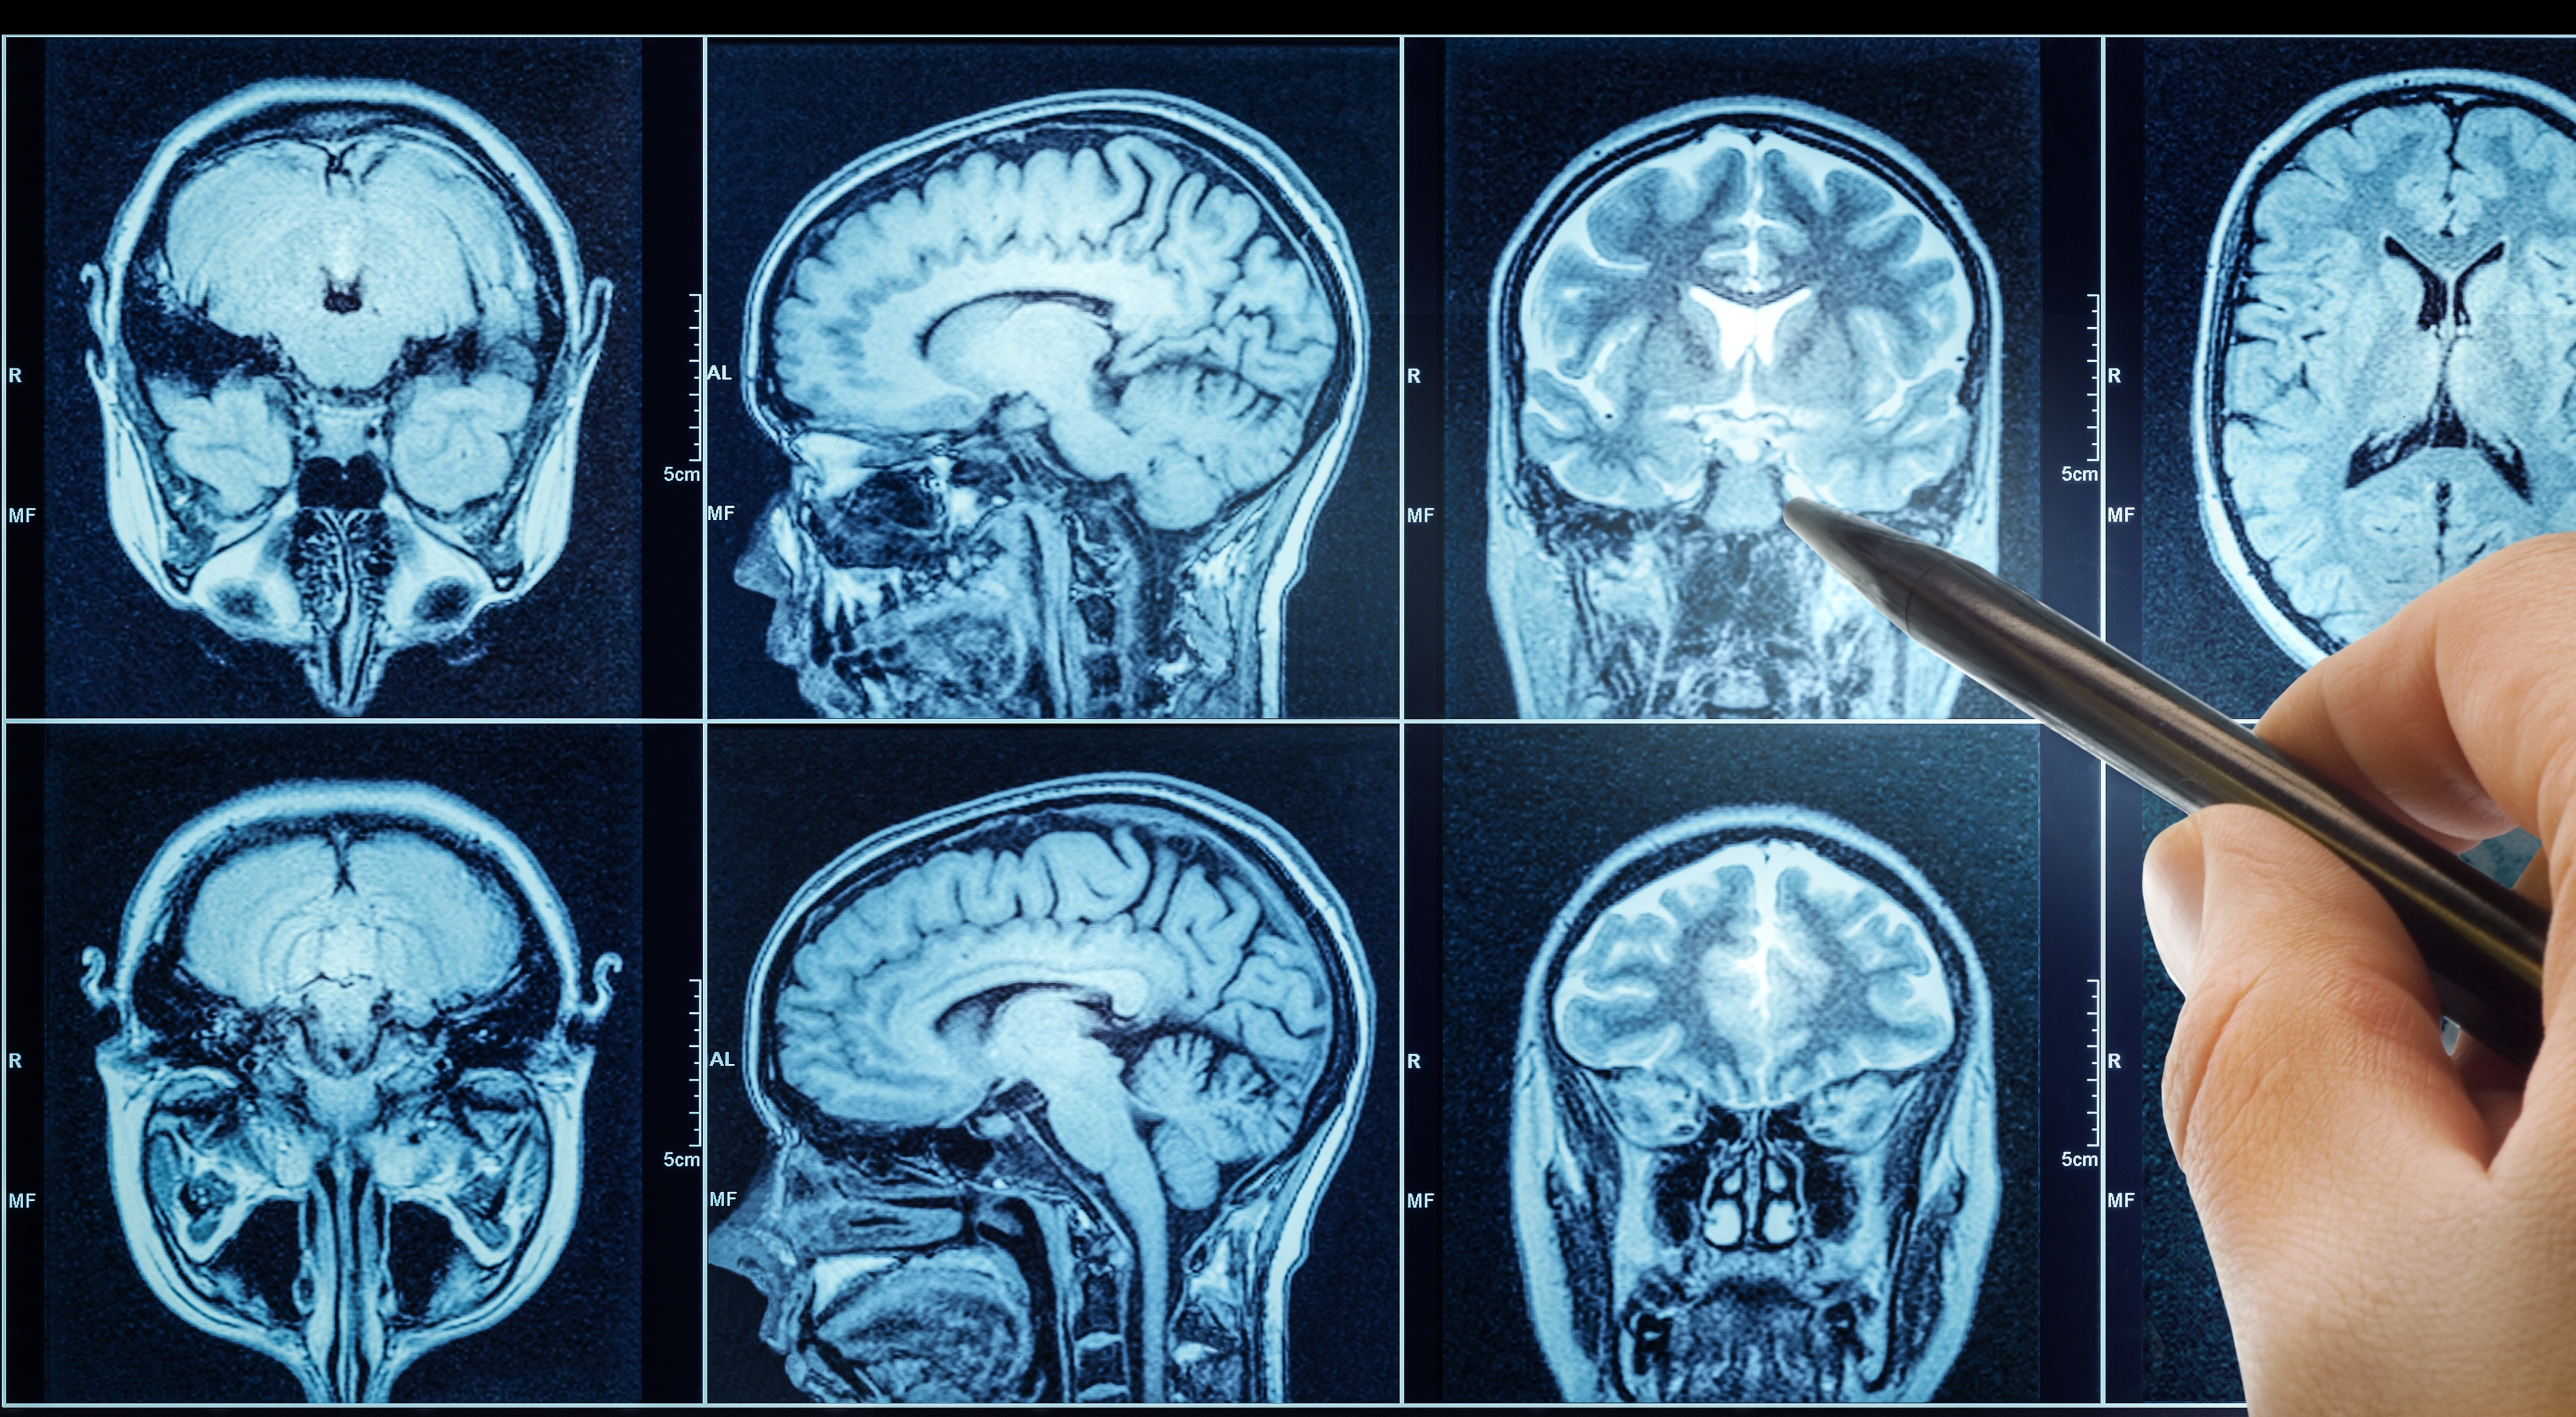

Dementia describes a collection of symptoms caused by disorders affecting the brain. It is not one specific disease.